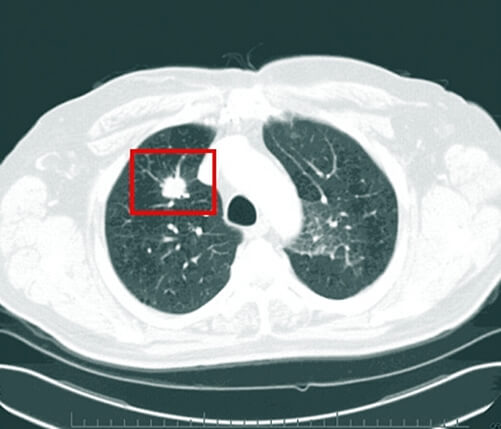

가장 앞에 오는 T는 'Tumor'의 앞 글자입니다. 'Tumor'는 종양을 뜻하는 말입니다. 즉, T는 폐암의 크기와 폐암의 상태를 나타내는 것을 뜻합니다.

폐암의 상태까지 같이 이해하려면 머리가 조금 복잡해질 수도 있습니다. 어려우신 분들은 그냥 '폐암의 크기구나'라고 생각을 하시면 됩니다.

2.2.1. T1

T1은 폐암의 크기가 3cm 이하를 뜻합니다. 그리고 폐암이 엽기관지 보다 더 근위부에 침범을 하지 않은 상태입니다. 또한 정확히 폐와 내장측흉막에 둘러싸여 있는 작은 상태일 때를 말합니다.

이 경우 5년 생존율이 80%가 넘습니다. 즉, 이때 외과적 수술로 치료를 받아야 완치율이 가장 높다는 뜻입니다. 그렇기 때문에 위에서 말한 주기적인 건강검진이 필수입니다.